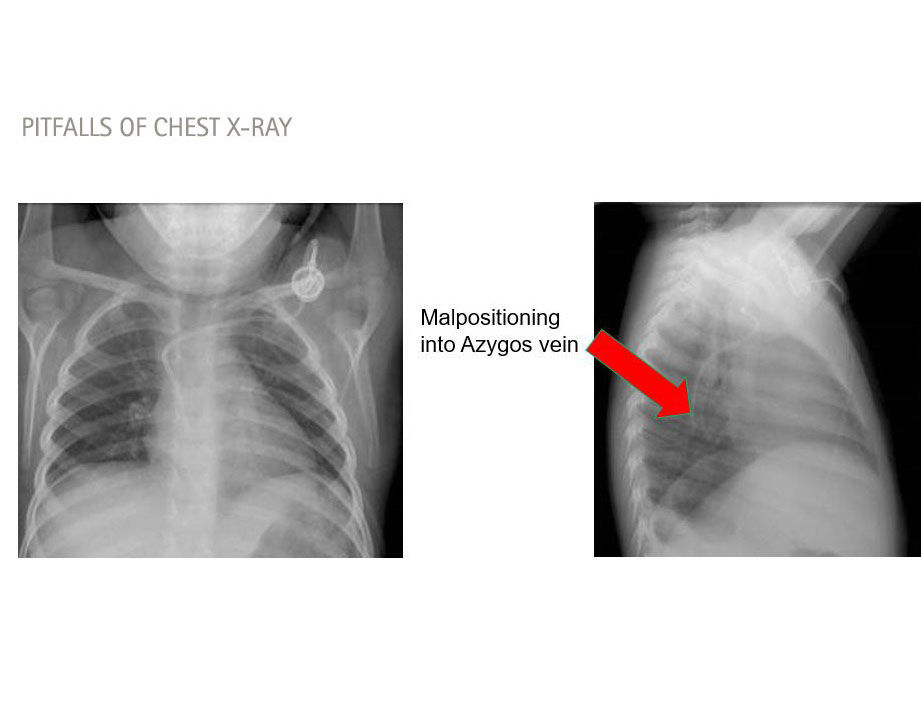

Azygos veinPericardium

Medica Image to detect misplaced catheter, chest X-ray, alternatively CT or MRI

Azygos vein; pleural diffusion pulmonary edema, dyspnea, chest pain, back pack pain